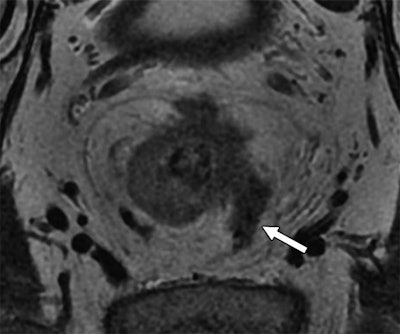

Above: MR image from a 55-year-old man with rectal cancer. Arrow indicates extramural venous invasion on T2-weighted image. Below: Rectal cancer in a 70-year-old man is evident (arrows and dotted line) using circumferential resection margin involvement on T2-weighted image. Images courtesy of AJR.Subjects were divided into a high-risk group (120 patients, 65%), with risk determined by factors such as a T3-stage tumor with a depth of more than 5 mm or T4-stage tumor, and a low-risk group (65 patients, 35%) with factors such as T1-, T2-, or T3-stage cancer with a depth of 5 mm.

Extramural venous invasion status is a key component in the evaluation of a tumor surrounded by muscle or containing red blood cells. Circumferential resection margin is used to determine the risk of local recurrence in an excised tumor.